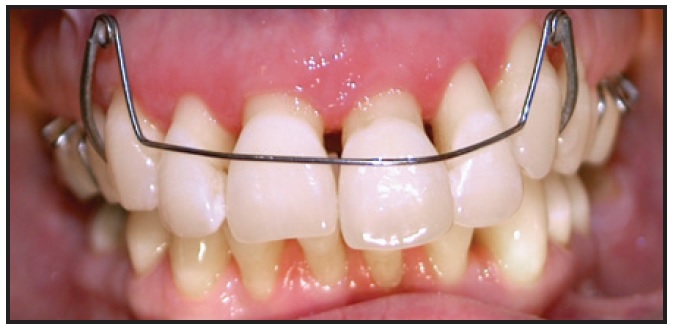

A minimally invasive flap was raised under local anesthesia, and the miniplate anchorage system was placed as described in previous reports.10 In the upper arch, the Bollard miniplates were inserted in the right and left infrazygomatic crests; in the mandible, they were placed between the canines and first premolars (Fig. 2).

Fig. 2 Surgical placement of Bollard** miniplates.

Two weeks later, the Herbst arms were attached to the laser-soldered nuts of the miniplates (Fig. 3).